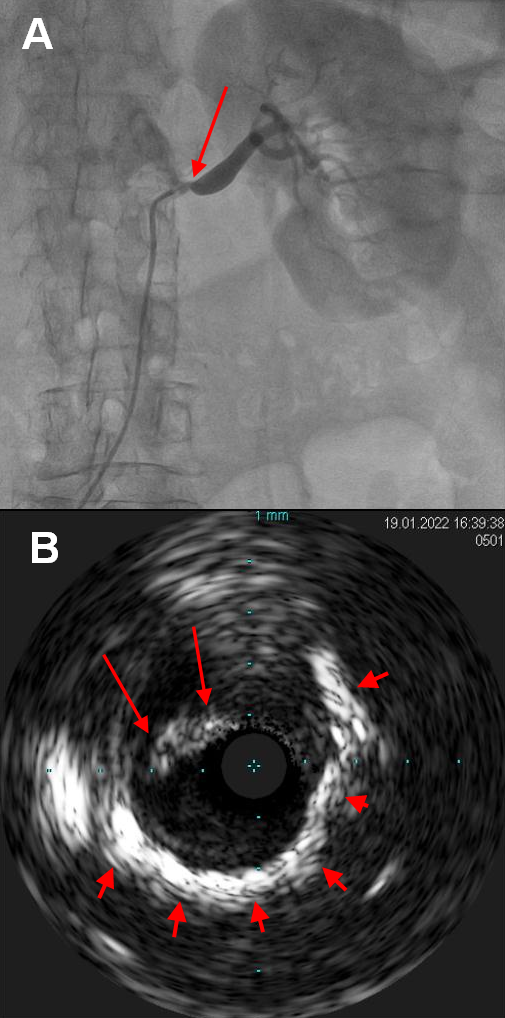

Renal artery angiogram through the right femoral artery demonstrated a critical severe (> 90%) ostioproximal left RAS (Figure 2A; Video 1) and a non-critical right RAS. Left renal artery was engaged with a 6-French renal double curve guide catheter, and a 300-mm 0.014-inch Regalia XS wire (Asahi) was advanced into a renal artery branch. Intravascular ultrasound (IVUS) showed a 6.0- to 6.2-mm reference diameter with metastenotic dilation up to approximately 7.5 mm, and severe superficial and deep calcification at the site of the RAS (Figure 2B). A Shockwave 5 x 60-mm intravascular lithotripsy (IVL) balloon was advanced across the lesion, and the guide catheter was withdrawn into the abdominal aorta. A total of 180 pulses was administered (6 cycles of 30 pulses each), as the initial cycles did not allow adequate expansion of the IVL balloon (Figure 3A, B; Videos 2 & 3). The lesion was then dilated with a 5 x 20-mm non-compliant balloon, and finally a 6 x 18-mm Express stent (Boston Scientific) was deployed with excellent angiographic result, which was confirmed with IVUS (Figure 3C-F; Videos 4-7).